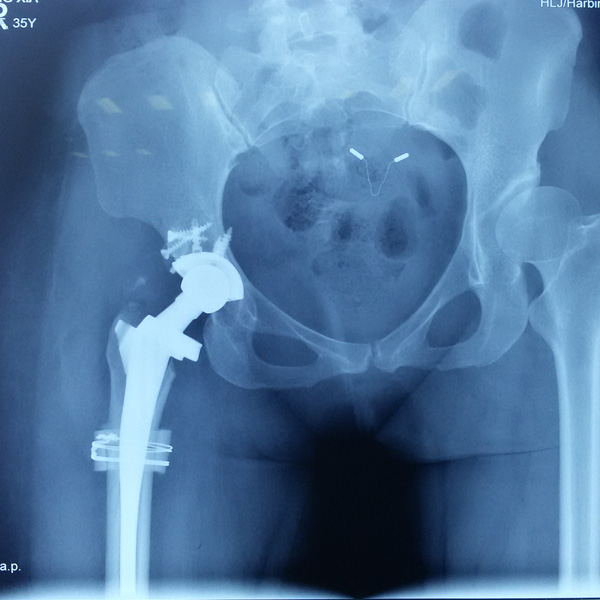

• 髖關節(jié)翻修髖關節(jié)翻修手術后手術前

髖關節(jié)翻修

患者蘇某,女性,11年前因“左髖關節(jié)屈曲攣縮畸形”行左側人工全髖關節(jié)置換,近來感覺左髖關節(jié)疼痛,不敢行走,經“攜生醫(yī)療平臺”就診于哈......